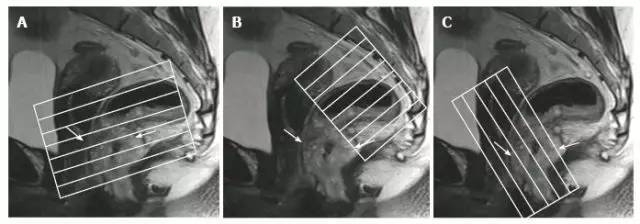

图 1. T2 加权矢状图像用于确定肿瘤纵轴,以便调整轴位和冠状位角度。A. 斜轴位在直肠肿块水平垂直于直肠壁;B. 斜轴位与盆底垂直,用于覆盖淋巴结引流区域;C. 冠状位与肛管平行,用于低位直肠肿瘤的成像。直肠肿瘤用箭头表示。